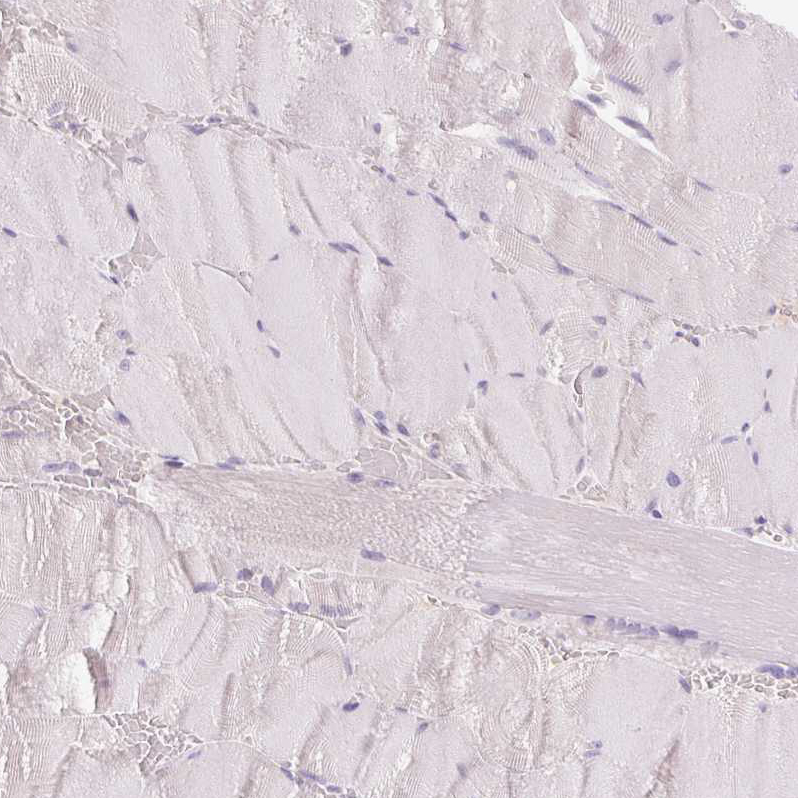

Immunohistochemistry analysis in human adrenal gland and skeletal muscle tissues using HPA057752 antibody. Corresponding CYP11B2 RNA-seq data are presented for the same tissues.